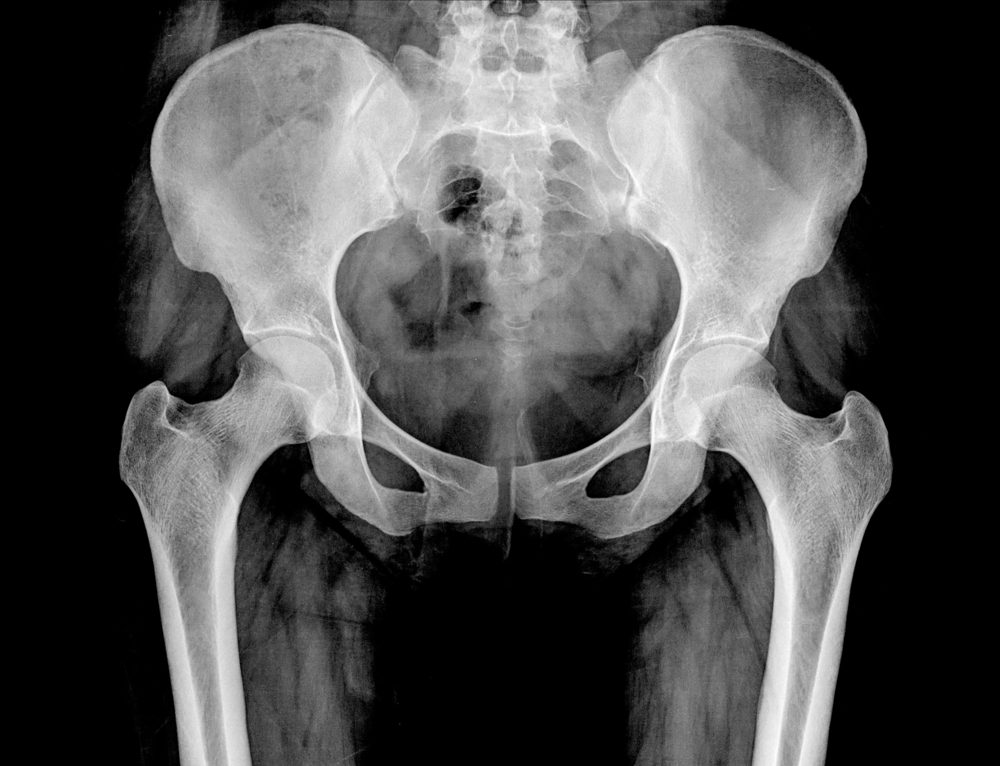

X-ray of the pelvis and spinal column of a woman

Xray Computer/Shutterstock

Pelvic inflammatory disease

If you experience a new pain in your lower abdomen and pelvis, an unpleasant vaginal odor, and pain or bleeding during intercourse, you should be tested for this inflammatory condition—it hits an estimated 88,000 American women between the ages of 15 and 44, according to the U.S.Department of Health & Human Services. “Sex may worsen the condition and cause a dull pain in the lower belly,” says Nicole Williams, MD, a gynecologic surgeon and founder of The Gynecology Institute of Chicago, IL. “See your healthcare provider immediately if you’re suffering from this sharp pain, as it usually does not resolve on its own and requires antibiotics as a course of treatment.”